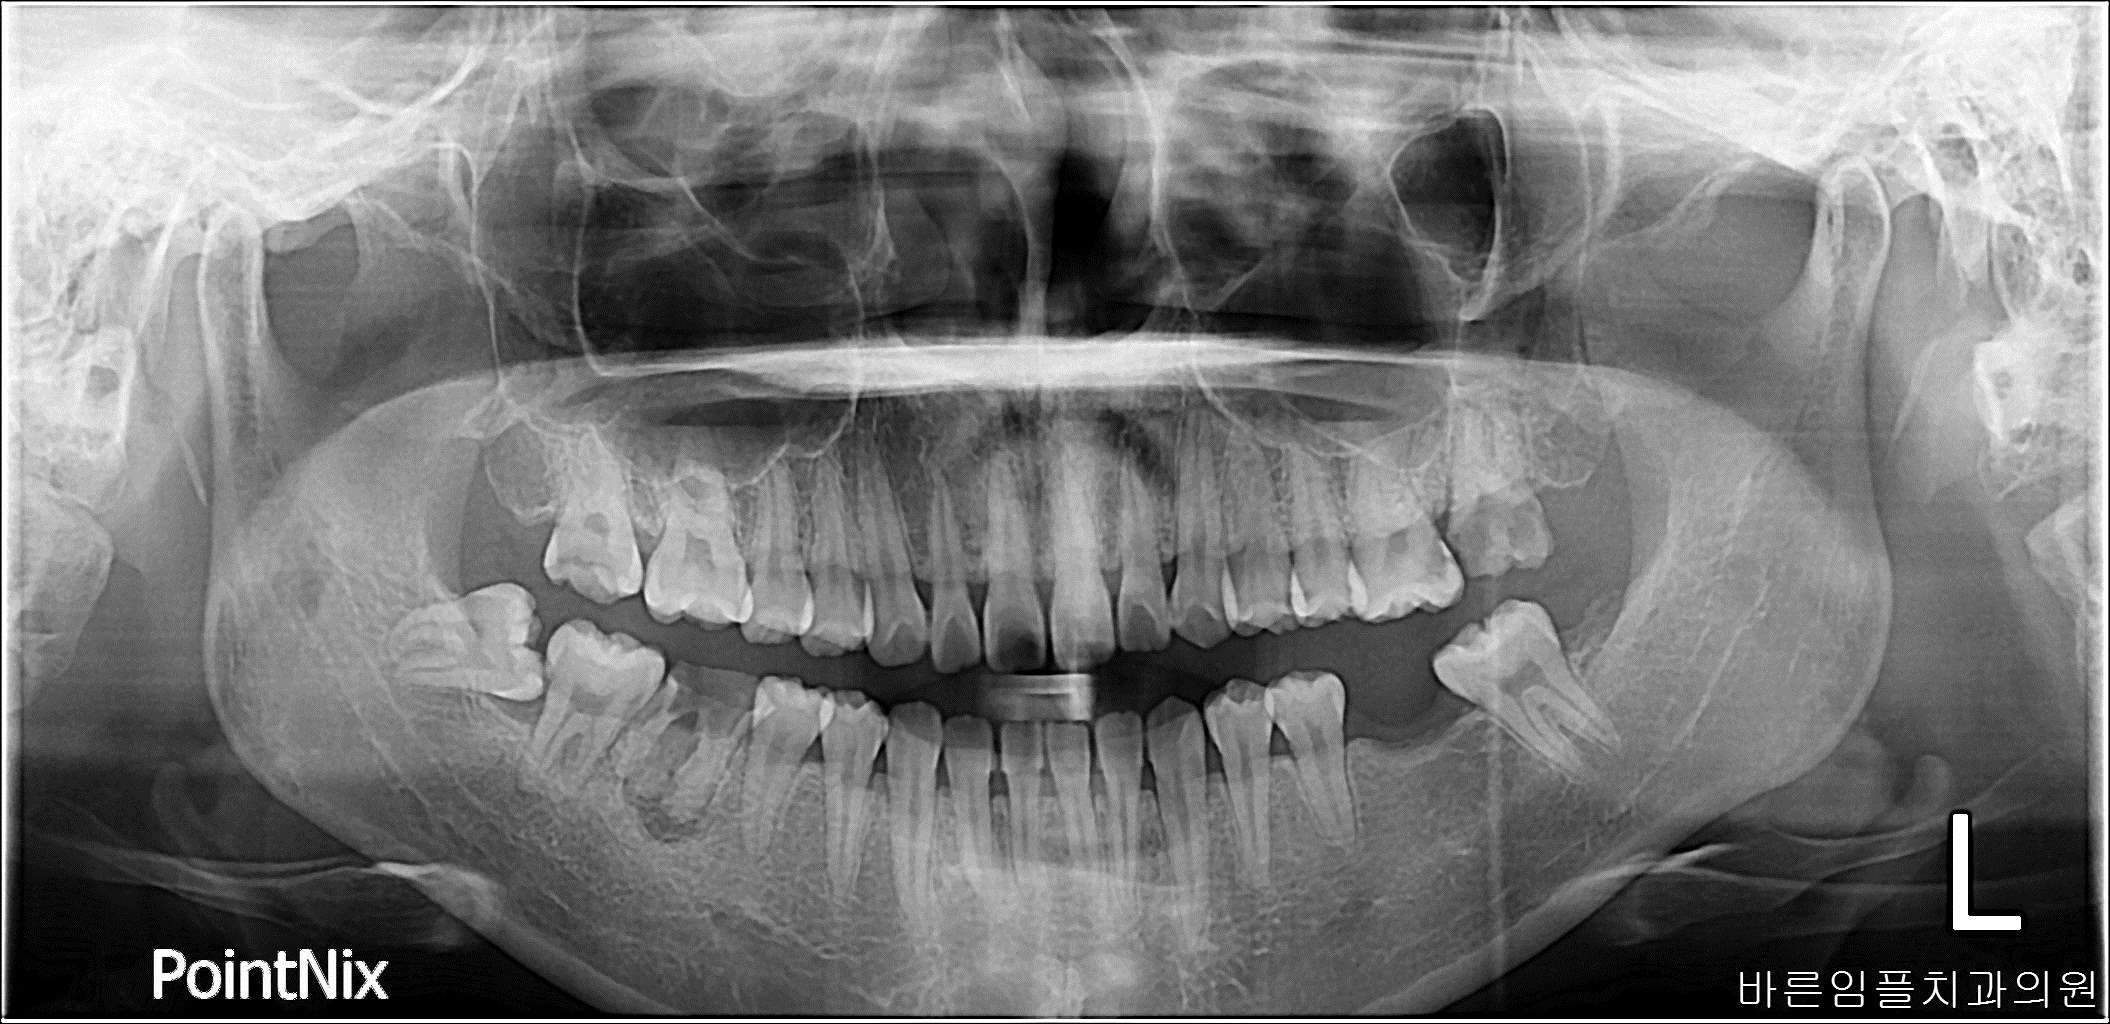

남ㅇㅇ / 임플란트 페이지 정보 작성일 23-10-27 17:02 2022-10-01 남ㅇㅇ Before 2023-09-02 남ㅇㅇ After 남ㅇㅇ / 임플란트 목록 이전글박ㅇㅇ / 수면임플란트 다음글 김ㅇㅇ / 수면임플란트